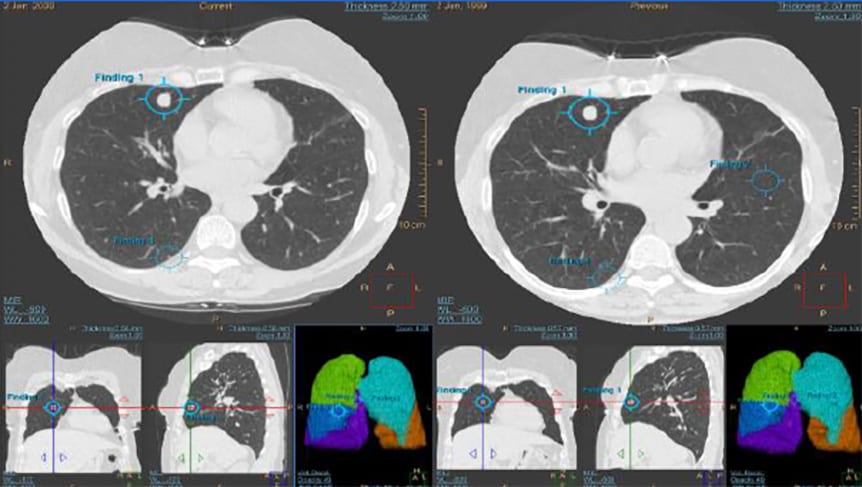

Die Herausforderung der konsistenten Erkennung wird durch strukturierte und automatische Auswertung auf der AVW – Advanced Visualisation Workstation unterstützt (z. B. LungRADS), was die Vergleichbarkeit erhöht und Folgeentscheidungen erleichtert.

Die Advanced Visualization Workspace (AVW) von Philips unterstützt Radiologen bei der effizienten Auswertung von Low-Dose-CTs im Rahmen des Lungenscreenings. Dank der Integration des ClearRead-Algorithmus von Riverain werden Lungenknoten schneller erkannt und charakterisiert. Über den Philips AI Manager lassen sich zudem weitere Algorithmen unterschiedlicher Hersteller einsetzen – nahtlos integriert in den klinischen Workflow. So profitieren Anwender von automatischer Lungen- und Lappensegmentierung, standardisierten Workflows nach Lung-RADS oder den Fleischner-Empfehlungen, einem integrierten Risikorechner sowie der automatischen Bereitstellung der Ergebnisse im PACS. Das Ergebnis: konsistente Befunde, höhere diagnostische Sicherheit und spürbare Zeitersparnis.